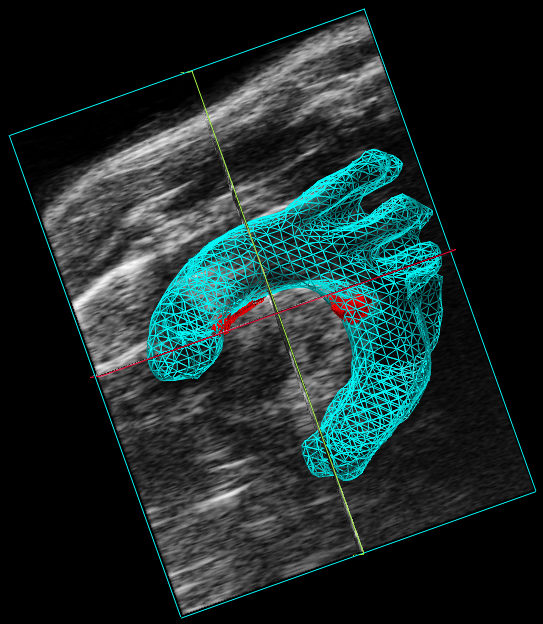

3D Reconstitution

With the 3D Mode you will see the entire shape of your target anatomy on a micrometer scale. 3D Mode allows for measurements of area, height, length and volume of the target anatomy.

Aortic arc

Combining 3D Mode with Color Doppler, Power Doppler, Non-Linear Contrast Mode or Photoacoustics sub-modes makes it possible to extract even more parameters such as depth, volume and percent vascularity, all at a micrometer scale.